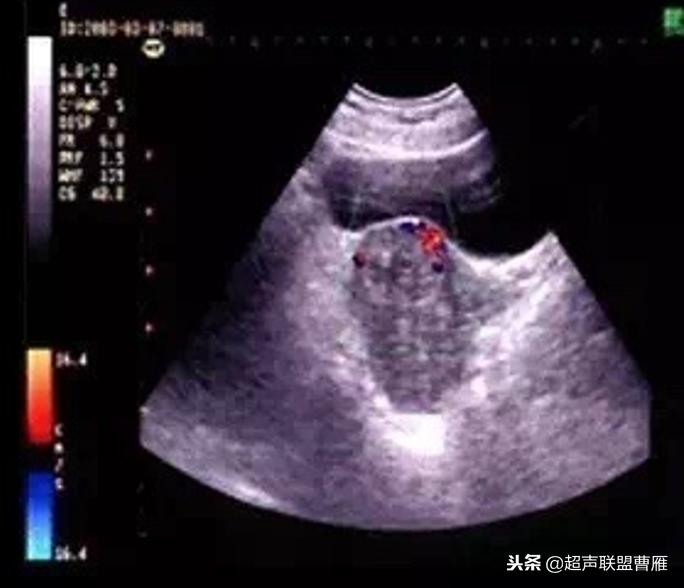

Ⅳ型绒毛退变型

1. 子宫下段见回声杂乱不均,范围较小,与局部肌层分界较清

2. 杂乱回声区内未见明显血流信号,无类滋养层周围血流频谱

(Ⅳ型绒毛退变型)